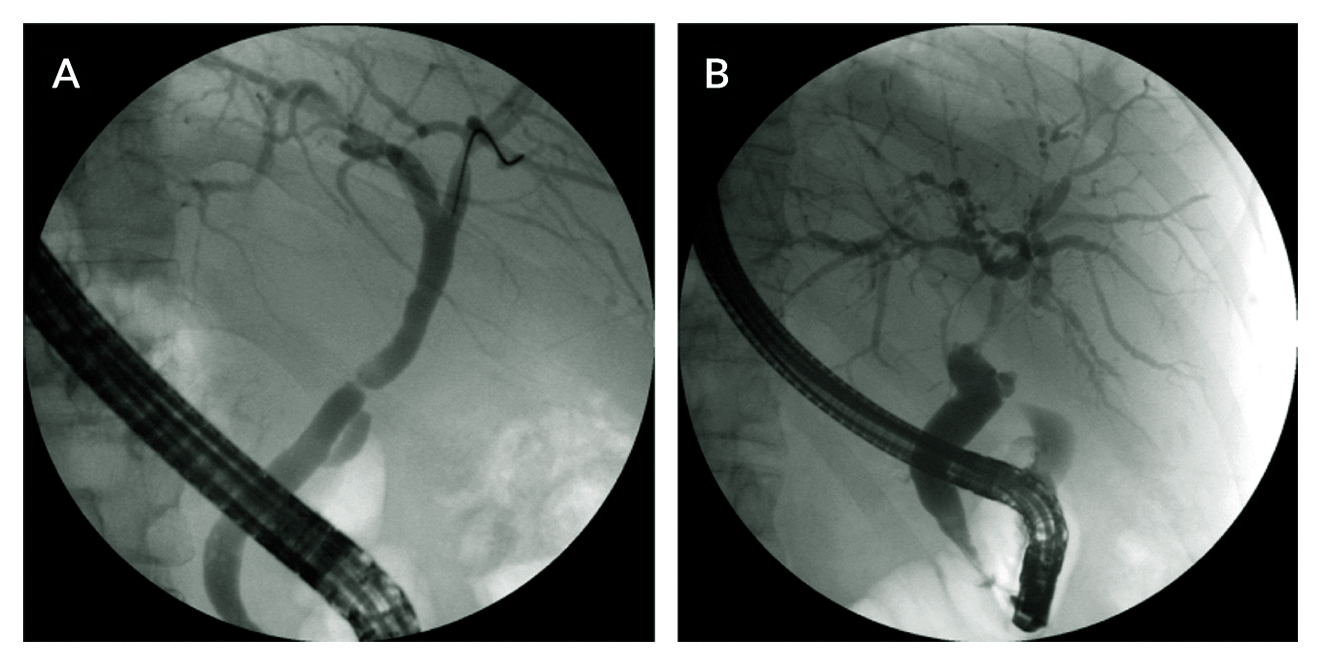

Figure 2. Cytomegalovirus (CMV) infection of the upper gastrointestinal tract. A. Livertransplanted patient complaining of dysphagia and epigastric discomfort with multiple longitudinal oesophageal ulcers seen at upper endoscopy. B. Endoscopic findings of deep oesophageal ulcerations with fibrinoid necrosis in another immunocompromised patient. In both cases, lesions were caused by CMV infection. Diagnosis depends on a positive mucosal biopsy, which should include specimens from the ulcer margins and ulcer base. Hematoxylin and eosin staining typically reveals “owl’s eye” cytoplasmic and intranuclear inclusion bodies.